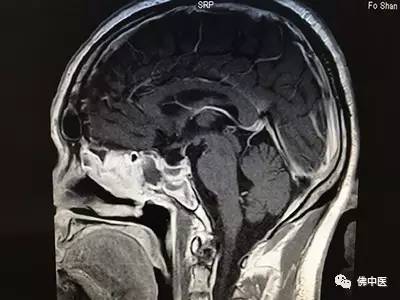

经验丰富的贾若飞主任接诊后,通过细致检查和阅片,确定刘先生患的是垂体大腺瘤,完全可以通过鼻腔微创手术切除肿瘤。术中,贾若飞带领专家团队成功为患者实施了内窥镜辅助下单鼻孔经蝶垂体瘤切除术。麻醉复苏后,患者激动地说:“我的头不痛了,感谢贾主任!”术后结合中医辨证施治以及优质护理,患者迅速康复,连连称赞佛中医不但环境好,专家实力更强,尤其是医护人员服务态度和敬业精神,让他充满了战胜病魔的信心。

术后